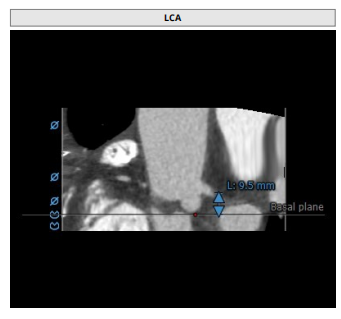

左冠高度:9.5mm

患者为三叶瓣,左右、右无疑似粘连,瓣叶明显增厚,轻度钙化。右冠高度10.9mm,左冠高度9.5mm,冠脉高度均较低。法式窦小,心脏角度不大,左室大小可,升主动脉未见明显增宽,病人整体结构小,瓣环仅有16.9mm,左室流出道16.7mm,窦管结合部23.9mm,升主动脉31.4mm。选择右股作为主入路。